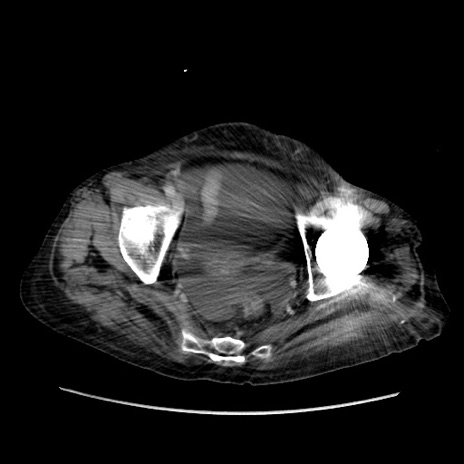

症例31(横断像)

【症例】80歳代 女性

【主訴】腹部膨満感

【現病歴】他院にて肝硬変にてフォロー中。1週間前から便秘、腹部膨満感、臍部腫瘤あり受診となる。

【既往歴】肝硬変

【身体所見】腹部膨隆あり、皮膚変化なし、疼痛なし。

【データ】WBC 4600、CRP 0.25